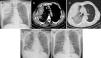

Chest X-ray revealed a heterogeneous opacity in the right upper lung field (Fig. 1A). Chest computed tomography (CT) showed a large subpleural hematoma on the right lung with 9cm in diameter and evidence of active bleeding (Fig. 1B), scattered infiltrate on the right upper lobe (Fig. 1C) and small right pleural effusion.

(A) Postero-anterior chest X-ray showing a heterogeneous opacity in the right superior lung lobe. (B) Chest CT showing a subpleural hematoma on the right lung with active bleeding. (C) Chest CT showing subpleural hematoma and scaterred infiltrate on the right upper lobe. (D) Postero-anterior chest X-ray performed at hospital discharge, showing reduction of the hematoma in the right superior lung lobe and right small volume pleural effusion. (E) Postero-anterior chest X-ray performed after 7 months, showing complete disappearance of hematoma.

The coagulation abnormality was corrected with vitamin K and 1000U of prothrombin complex concentrate and he was admitted to intensive care unit. Surgery was not performed after consultation with thoracic surgeons. He presented a gradual reduction of hemoptysis but right pleural effusion increased. A right diagnostic thoracentesis was performed and the fluid was serosanguineous, not compatible with hemothorax (pleural fluid hematocrit less than 50% of the peripheral blood hematocrit), however, given the large volume of the pleural effusion, conditioning dyspnea and respiratory failure, a chest tube was inserted during 5 days. Fiberoptic bronchoscopy was performed and excluded endobronchial lesions, bleeding or foreign body. He required transfusion of 3 units of packed red blood cells during hospitalization. The case was discussed with cardiology and, given the embolic risk associated with permanent atrial fibrillation, treatment with warfarin was restarted (with discontinuation of aspirin) and the INR maintained within the therapeutic range, without hemoptysis recurrence. The pulmonary hematoma had a progressive size reduction (Fig. 1D) and after 7 months of follow-up, chest X-ray shows complete disappearance of hematoma (Fig. 1E).